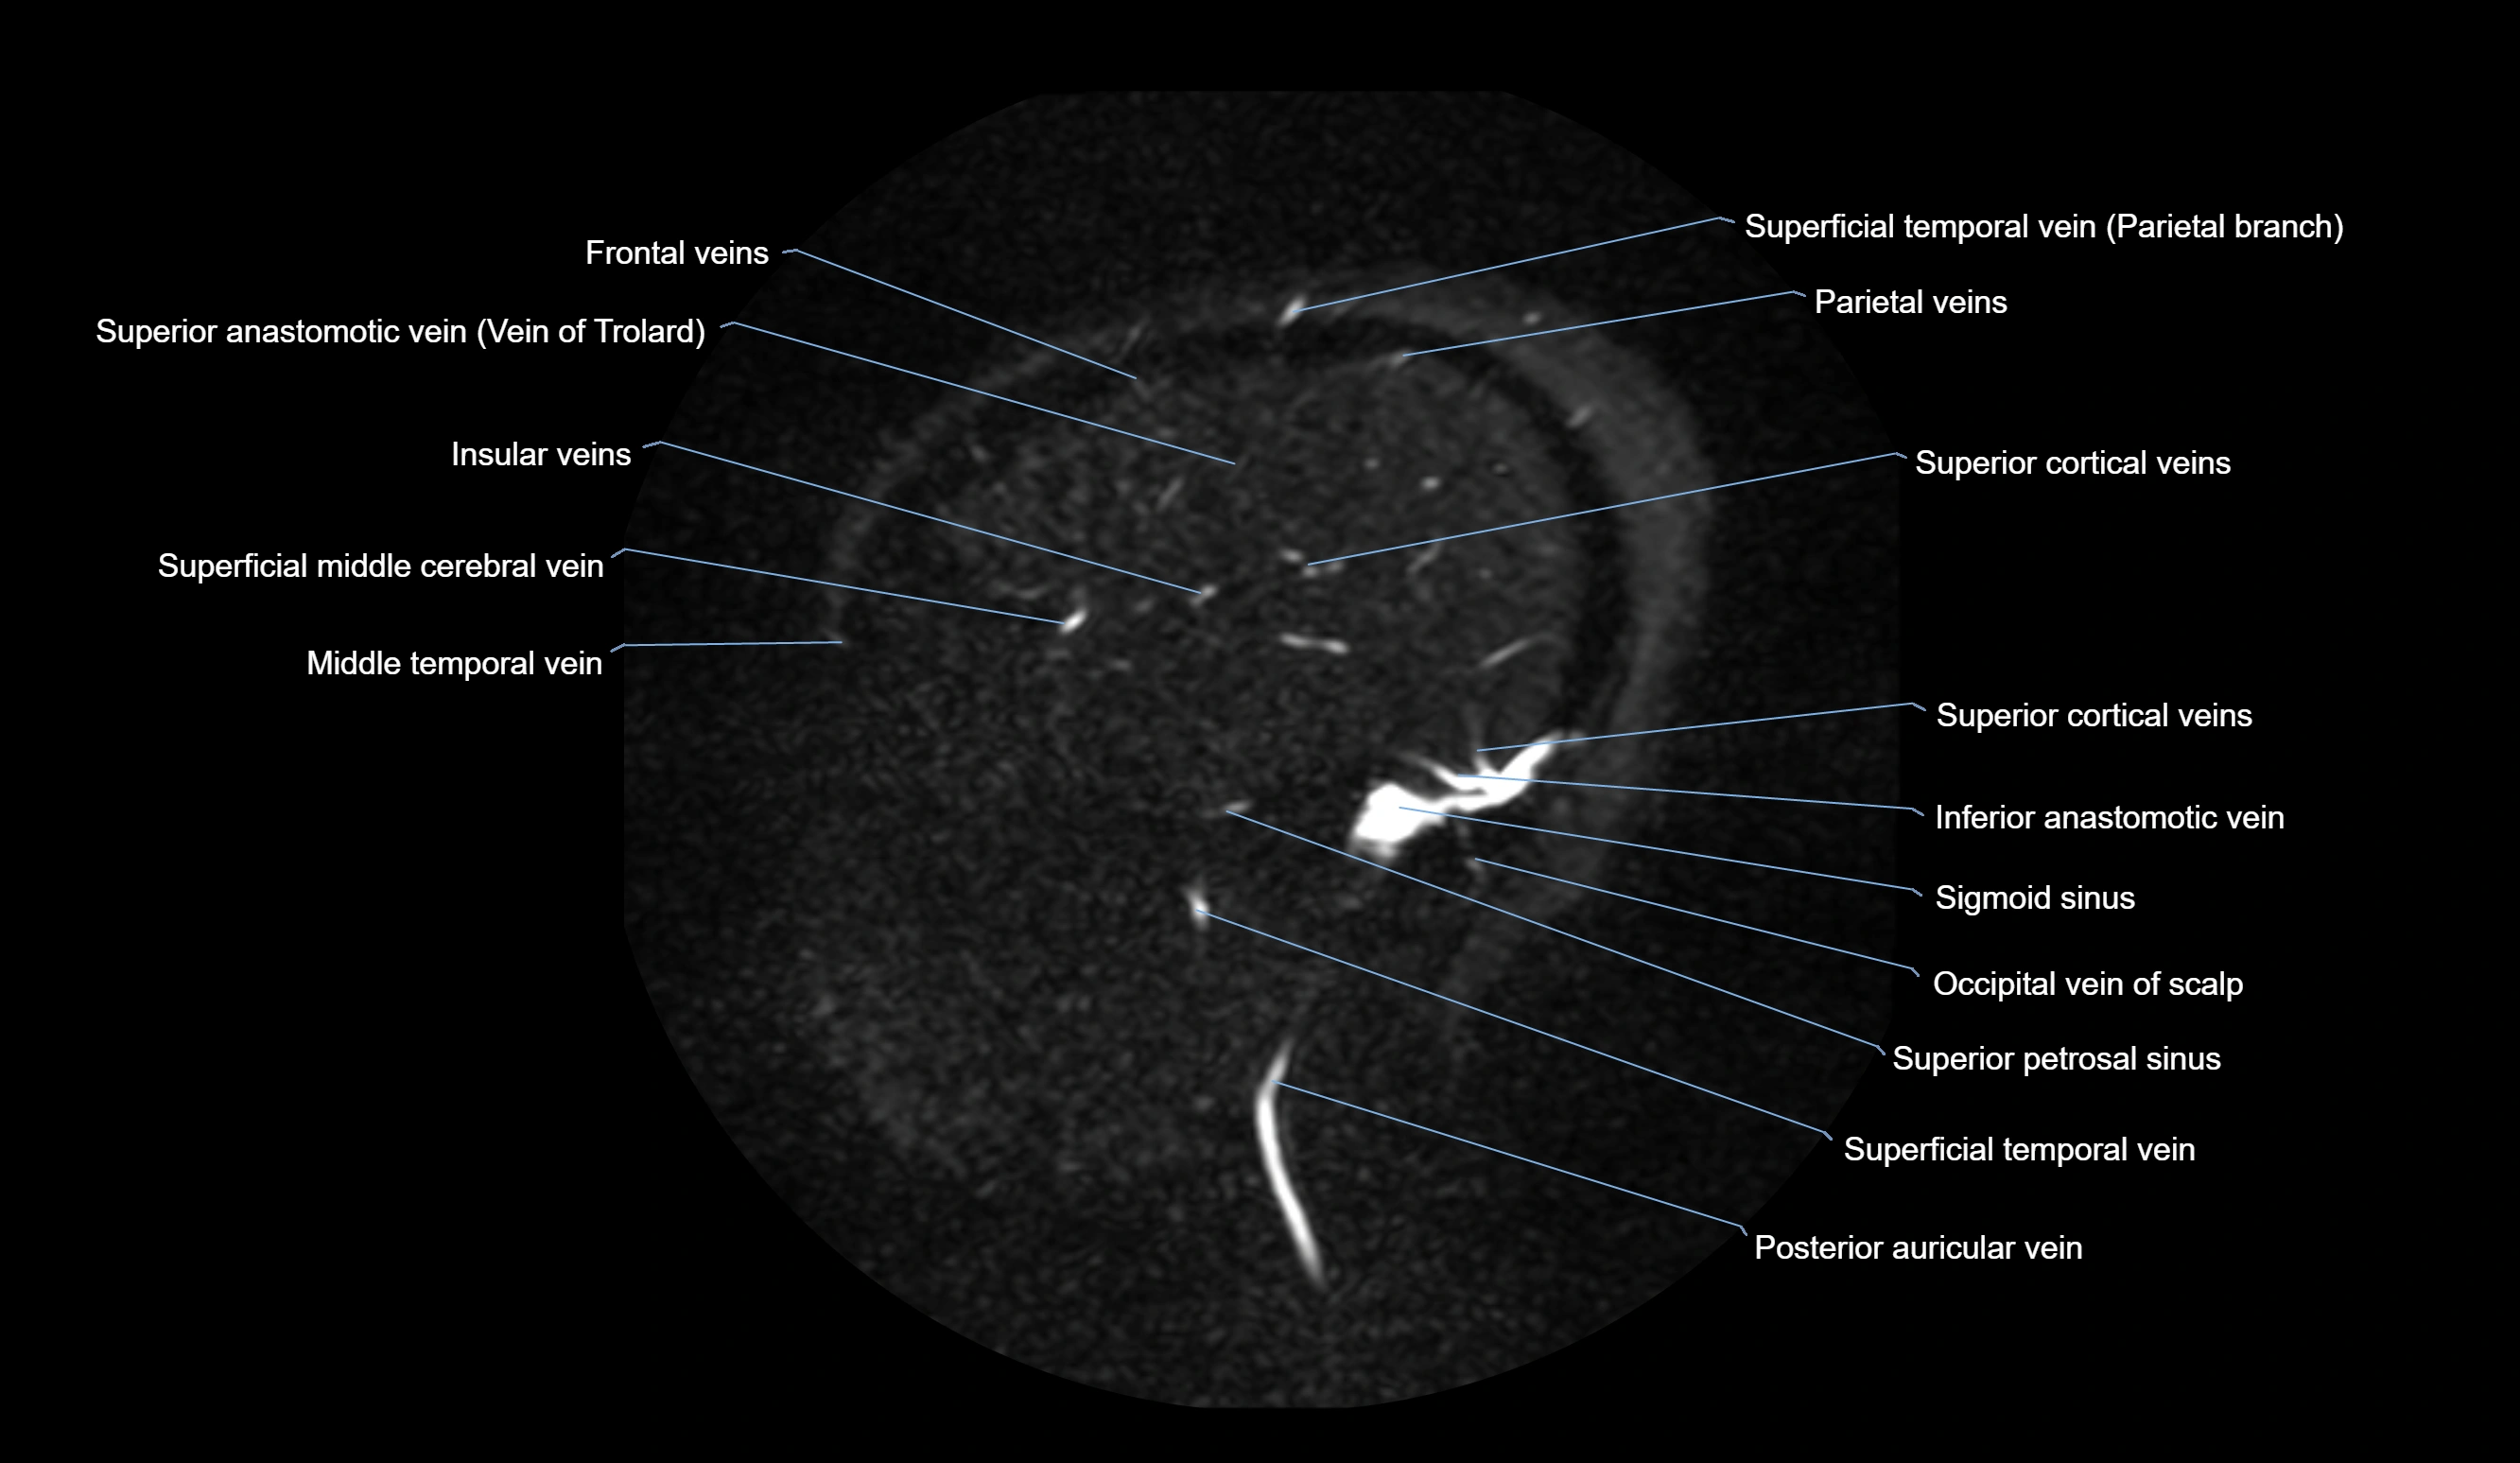

MR Venography (MRV):

• Time-of-flight (TOF) or contrast-enhanced MRV shows the angular vein as a bright enhancing venous channel

• Clearly demonstrates its continuity with the facial vein and superior ophthalmic vein

• MRV is highly useful in evaluating thrombosis, venous obstruction, or collateral venous drainage